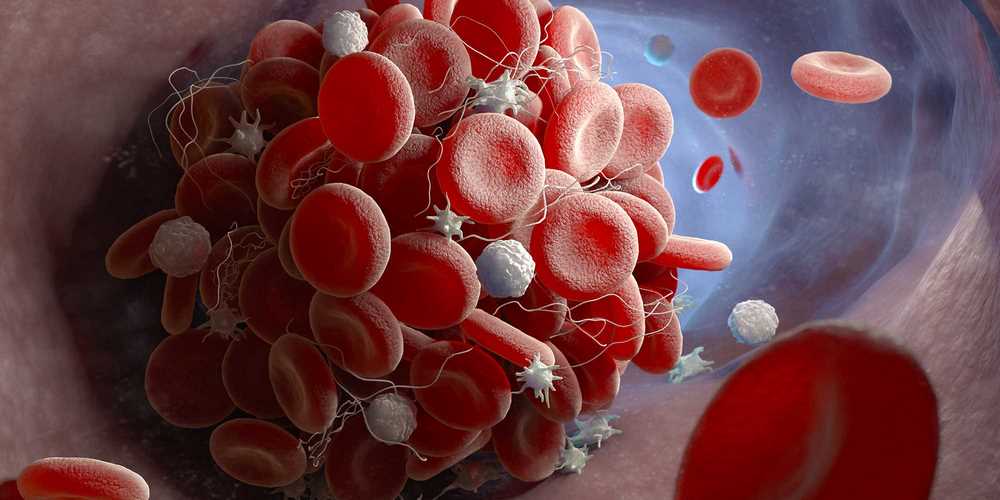

Jeśli obawiacie się zakrzepów krwi mogących powstać po przyjęciu szczepionki AstraZeneca lub Johnson&Johnson, podpowiadamy na jakie sygnały zwrócić uwagę.

Zdarzenia zakrzepowo-zatorowe po szczepionkach wektorowych przeciw COVID-19 są bardzo rzadkie, niemniej przyczyny tych zdarzeń wymagają wyjaśnienia – podkreślają polscy naukowcy i w swojej publikacji w czasopiśmie...